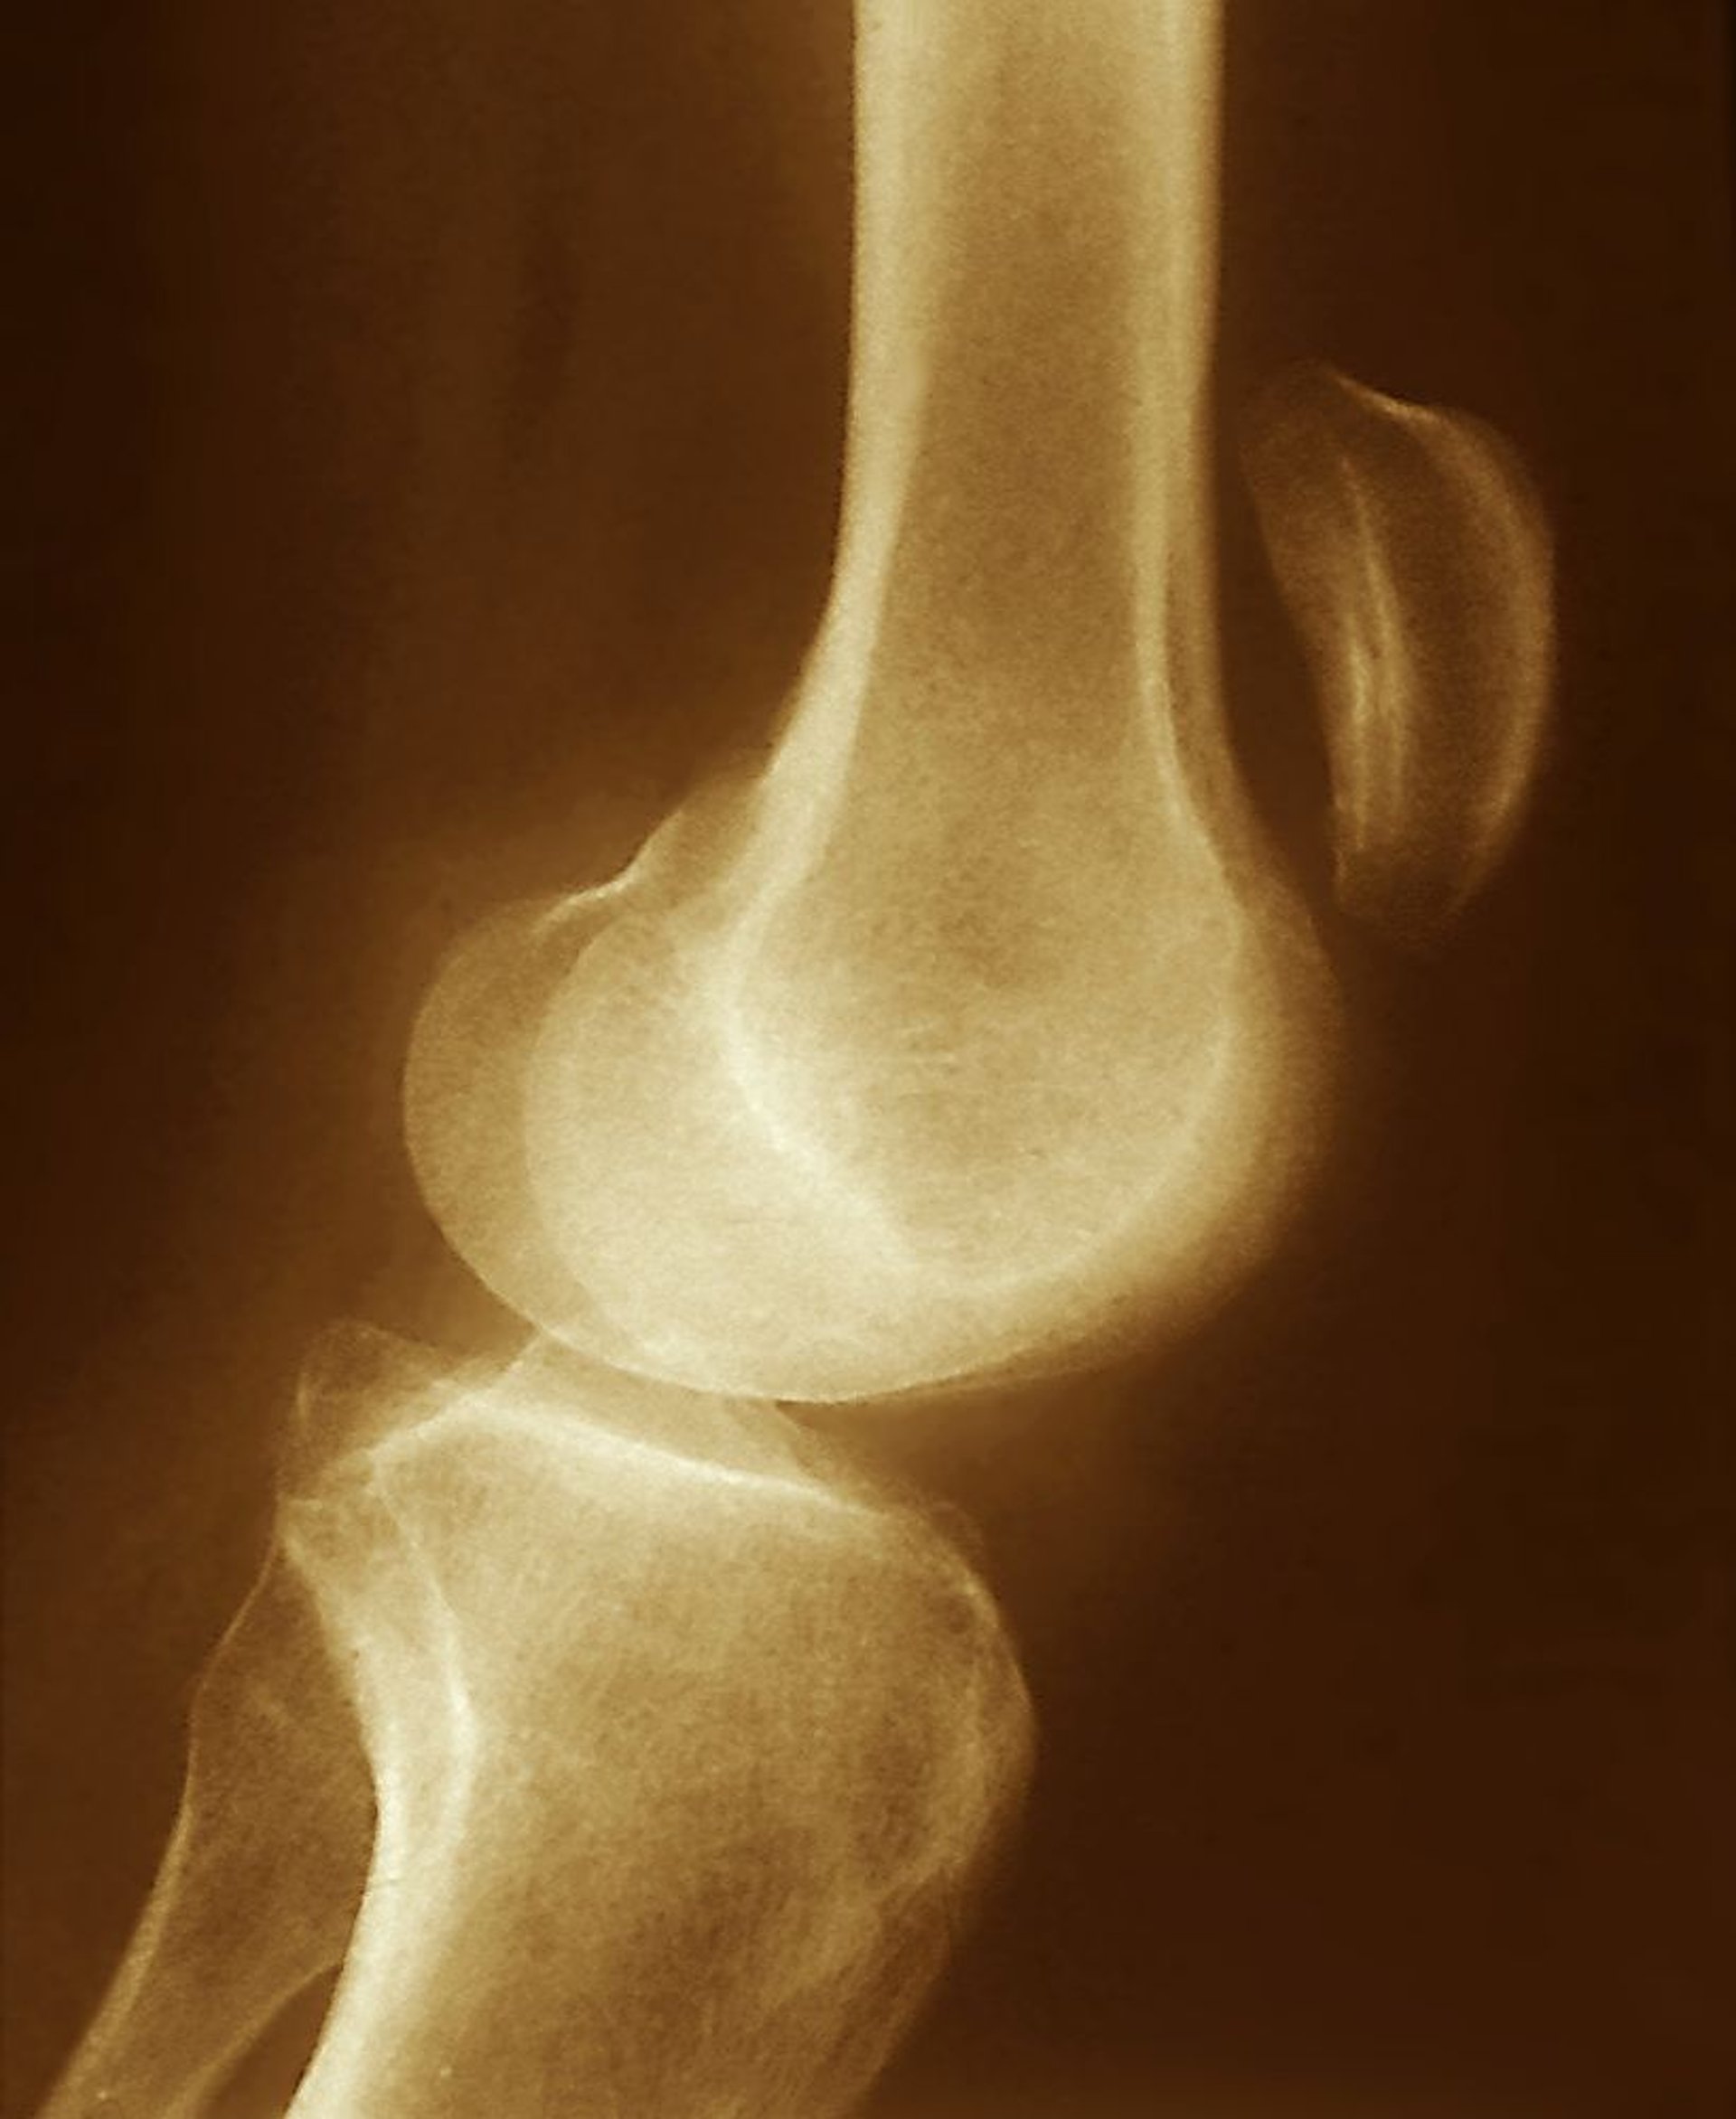

Разрыв сухожилия надколенника

На этом рентгеновском снимке видно смещение коленной чашечки вверх (значительно выше коленного сустава), что указывает на разрыв надколенника, с беспрепятственным сокращением четырехглавой мышцы.

ZEPHYR/SCIENCE PHOTO LIBRARY